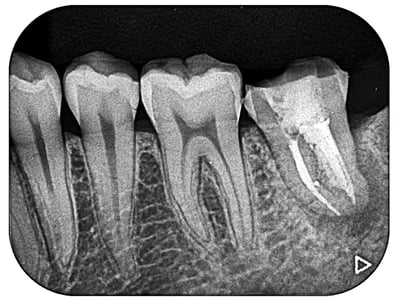

歯根の周囲には、歯根を取り巻くようなX線透過があります。(炎症があるということです)

根管の中には、ガッタパーチャという天然ゴムの根管充填材がありますが、これが緊密に歯根の尖端まで充填(詰め)されていないので、このような状態となっています。まずは、このガッタパーチャを完全に除去することが重要です。